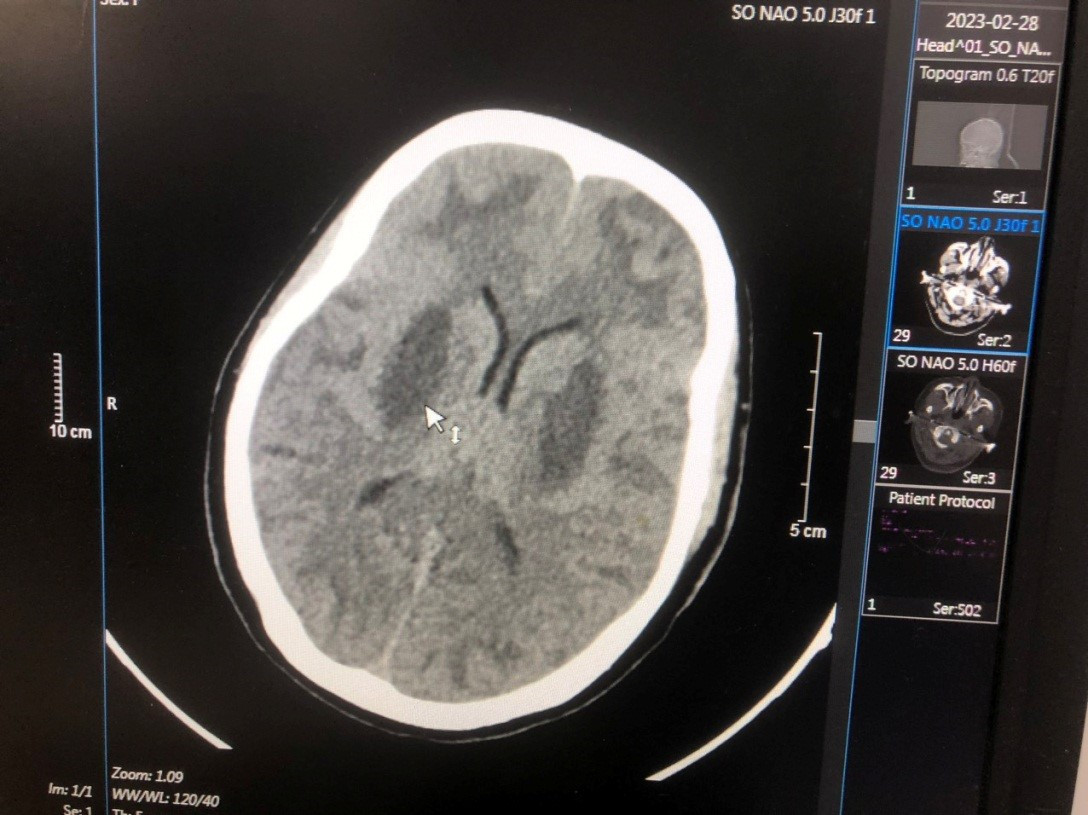

| Hình ảnh tổn thương não của anh Triệu Văn N. |

Bệnh nhân nặng tiếp theo là Triệu Văn N. (17 tuổi, dân tộc Dao, quê Cao Bằng) vào viện ngày 24/2. Bốn ngày trước khi vào viện, bệnh nhân thấy khó thở, mệt, mờ mắt, lơ mơ, hôn mê, ngừng thở. Bệnh nhân được đưa đến Bệnh viện đa khoa tỉnh Bắc Ninh cấp cứu. Sau đó được chuyển tới Trung tâm Chống độc Bạch Mai trong tình trạng hôn mê, tụt huyết áp, nhiễm toan chuyển hóa nặng, tổn thương não nặng hai bên, nồng độ methanol trong máu là 125 mg/dL, không có ethanol. Bệnh nhân đã được cấp cứu điều trị hồi sức giải độc lọc máu, hiện tri giác có cải thiện nhưng não vẫn tổn thương và phù não nhiều, tổn thương mắt.